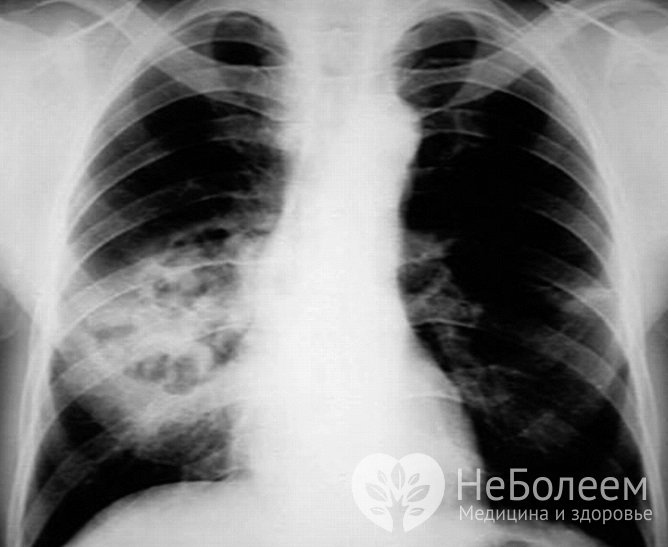

Пневмония – это заболевание, при котором воспалительный процесс поражает разные структуры легких. Болезнь может быть первичной или стать осложнением другой патологии.

Если есть подозрение на воспаление легких, необходимо обратиться за консультацией к терапевту. После опроса проводится необходимый осмотр:

Для постановки диагноза врач проводит осмотр, включающий аускультациюПри подозрении на развитие заболевания проводятся следующие исследования: